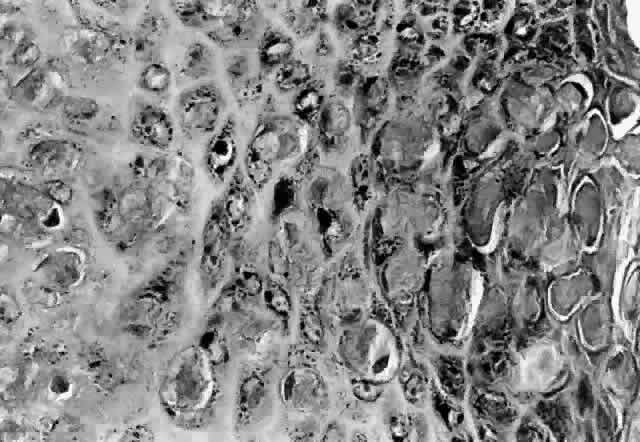

HPV-induced conjunctival squamous papillomas demonstrate papillomatosis, acanthosis, and koilocytosis (Fig. 6). Because they are mucous membrane lesions, those of the conjunctiva and lacrimal sac show no granular cell layer but will show keratinization if they are large or exposed (Fig. 7). In our experience the frequency of koilocytes is variable, even in lesions almost certain to be viral (Fig. 8). Scattered inflammatory cells may be present in the cores or epithelium. Virus can be detected immunohistochemically in the nuclei of the cells (Fig. 9).

Fig. 6. Eyelid papilloma, histology. High-power view of acanthotic epithelium and koilocytes. (Original magnification × 400)

Squamous papillomas of the eyelid are exophytic lesions with multiple fronds, each showing acanthotic epithelium around a fibrovascular core. There is typically hyperkeratosis and koilocytosis. Inflammatory cells may be present.